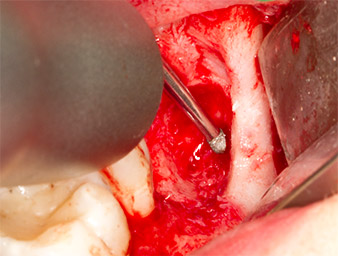

Per ottenere materiale autogeno per il successivo trattamento della ferita, sono stati estratti frammenti di osso sano nella zona del residuo di radice con uno strumento piezochirurgico (Piezomed B5) (Fig. 5).

Il tessuto autogeno è stato rimosso con la sezione a forma di raschietto della parte funzionante dello strumento e conservato un una soluzione salina fisiologica per uso successivo (vedere Fig. 13).